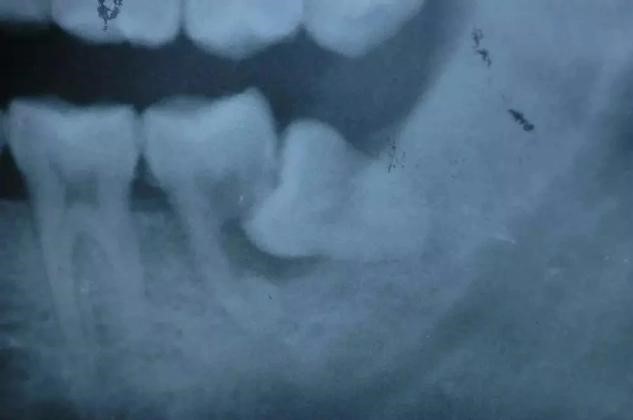

2、磨牙龋齿:对于向前倾斜的阻生智齿,食物通常积聚在相邻牙齿之间,这容易导致相邻牙齿(下第二磨牙)的龋齿。这种龋齿不容易被发现,一旦出现疼痛(急性牙髓炎),牙冠通常会严重受损。出现龋齿、牙髓炎,甚至牙齿不能保留。第二磨牙缺失对咀嚼功能有很大影响,也很难用义齿修复。

1、冠周炎:智齿冠由于嵌塞不能完全暴露,食物和细菌很容易积聚在牙冠周围的牙龈粘膜下层(盲袋)中,引发冠周炎。冠周炎通常无症状,当感冒或疲倦时,由于全身抵抗力下降,会变成急性冠周炎,出现面颊肿胀、张口困难、吞咽疼痛、全身发热等症状。如果仍然不拔牙,并允许反复攻击,可能会形成皮下脓肿或口腔部分的瘘管,进而影响面部。